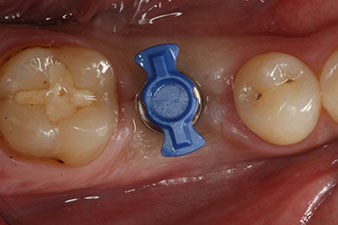

Implantmed

Fig. 7: Display of the ISQ value on the Implantmed: A separate device is not required and the values are documented along with the other values for preparation of the implant bed and insertion.

After healing of the soft tissue, the implant stability was measured again before delivery of the prosthetic restoration.

Both values were virtually unchanged and were between the medium and the high range – where the lower value is always used as the reference value that determines the treatment.

Therefore, successful osseointegration and adequate biological stability could be recorded, which enabled an impression to be taken in the same session.